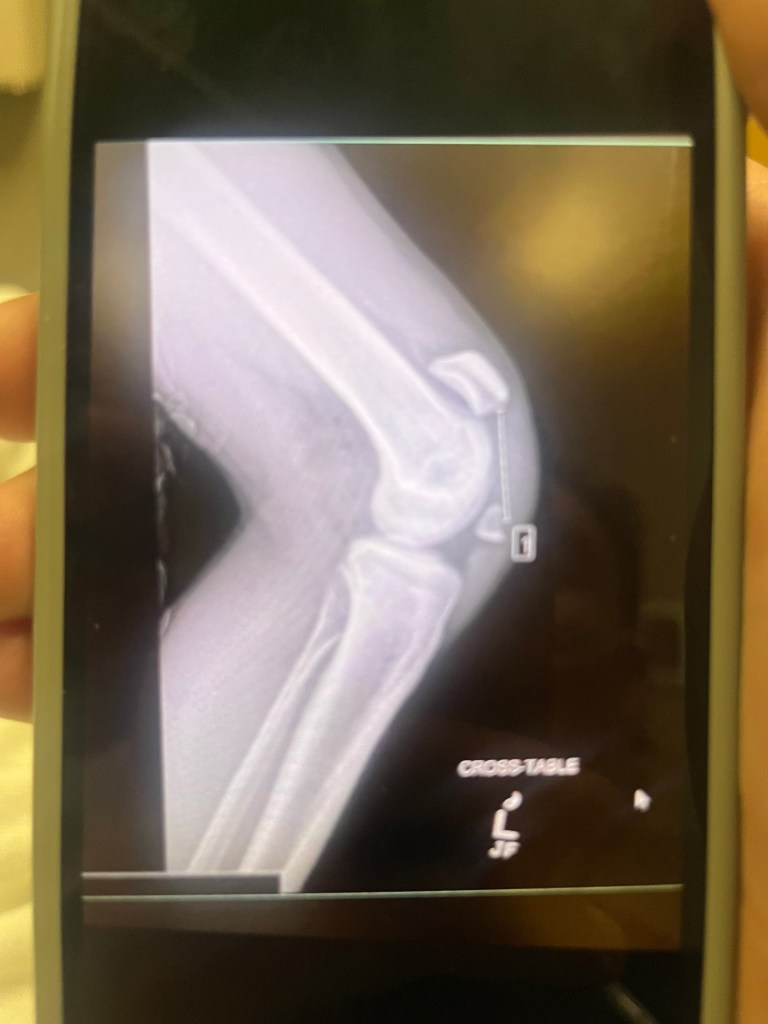

I recently sustained a nasty knee injury while snowboarding, fracturing my left kneecap in two which resulted in me getting surgery to fix it. What messed me up the most about this knee injury is how it was my own body that caused it. I didn’t hit my knee on anything or fall in any weird way while on my snowboard; I landed a jump and next thing I knew I was screaming like my life depended on it in the middle of Bluebell at Winter Park. Sorry to instill a new fear for you snowboarders or skiers, but I like to think that I just got real unlucky. As a result, I am in a knee brace for about 6 more weeks, rendering me pretty unable to get back to doing the things I love doing for what feels like a lifetime.